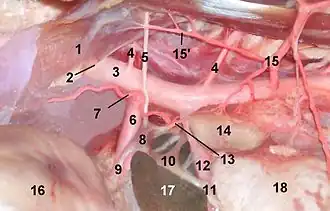

Celiac and cranial mesenteric ganglion . 1 Crus sinistrum (Diaphragma), 2 hiatus aorticus, 3 Aorta, 4 Arteria lumbalis, 5 Nervus splanchnicus major, 6 Arteria coeliaca, 7 Arteria phrenica caudalis, 8 Celiac ganglion, 9 Plexus coeliacus, 10 Inferior mesenteric ganglia, 11 superior mesenteric plexus, 12 Superior mesenteric artery, 13 Nervus splanchnicus minor, 14 Adrenal gland, 15 Arteria abdominalis cranialis, 16 Stomach, 17 Liver (Lobus caudatus), 18 Kidney | |